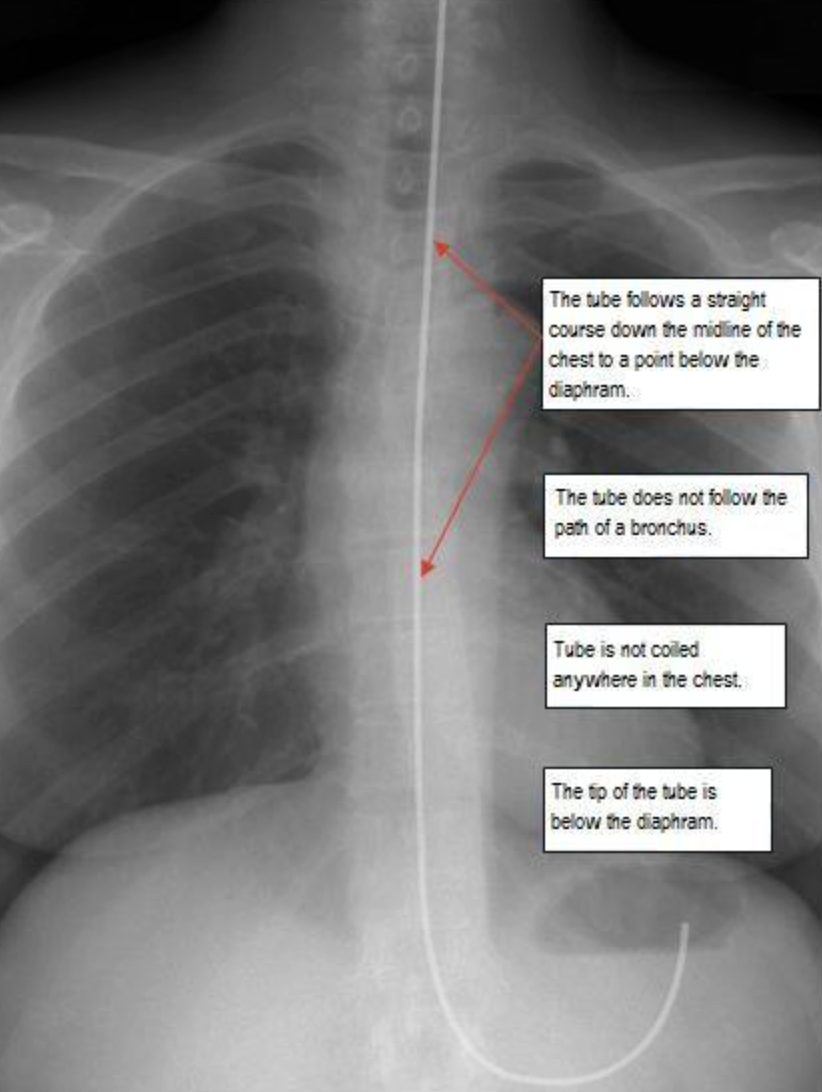

D) X-ray GOLD STANDARD to check - a tube passing center of chest, passing diaphragm, tip below tip of diaphgramgm ((THREE FINDINGS SHOULD BE PRESENT))

X-ray placement - Mention

1- follows straight course through midline to below diaphram

2- tube not follow bronchus path

3- not coiling

4- tip tube below diaphragm